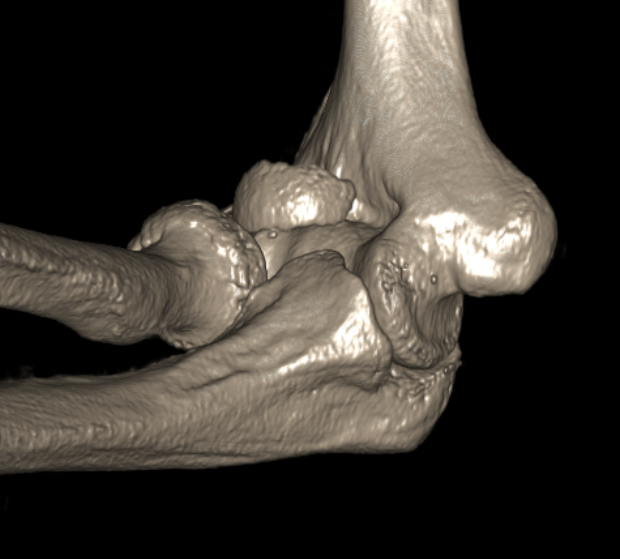

capcapcap

Capitellum fracture with radial head fracture

capcap

Capitellum fracture with radial head dislocation due to LCL injury